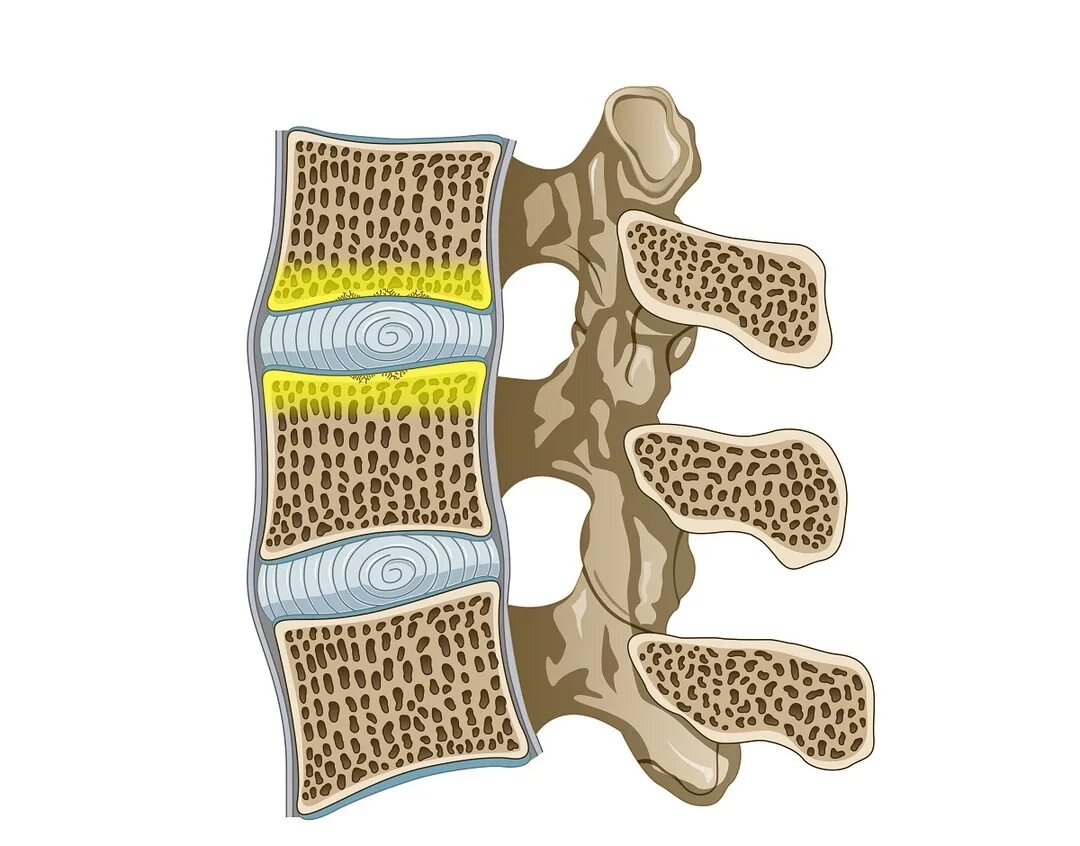

Изменение по типу modic 1